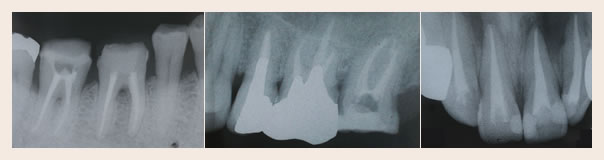

治療終了後のレントゲン写真